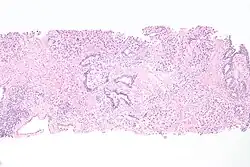

Histopathology of urothelial carcinoma of the urinary bladder. -